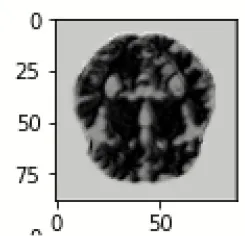

The database used in this study consists of a total of 6,200 AD images that are retrieved from the Kaggle database. It comprises grayscale images of 896 MD, 64 Mod D, 3,200 ND, and 1,966 VMD images, with a dimension of (208 × 176 × 3) pixels. The dataset for evaluation is divided in such a way that 80% of the image samples are utilized for training the model and the remaining 20% are utilized for testing the model (Filipovych et al., 2011). Figure 2 shows the database of MRI images. Table 2 shows the publicly available AD dataset.

FIGURE 2

www.frontiersin.org

Figure 2. Alzheimer's disease: (A) M.D, (B) Mod.D, (C) N.D, and (D) V.M.D.